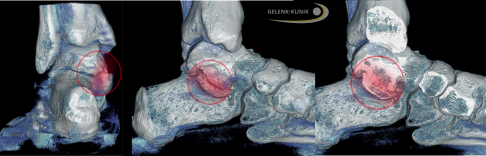

Digitale Volumentomographie einer inkompletten Coalitio calcaneonavicularis. Zwischen dem rechts liegenden Kahnbein und dem links oben liegendem Fersenbein besteht eine Brücke aus Bindegewebe. © Gelenk-Klinik

Darstellung einer vollständigen Coalitio talocalcanearis in DVT und Röntgen. © Gelenk-Klinik